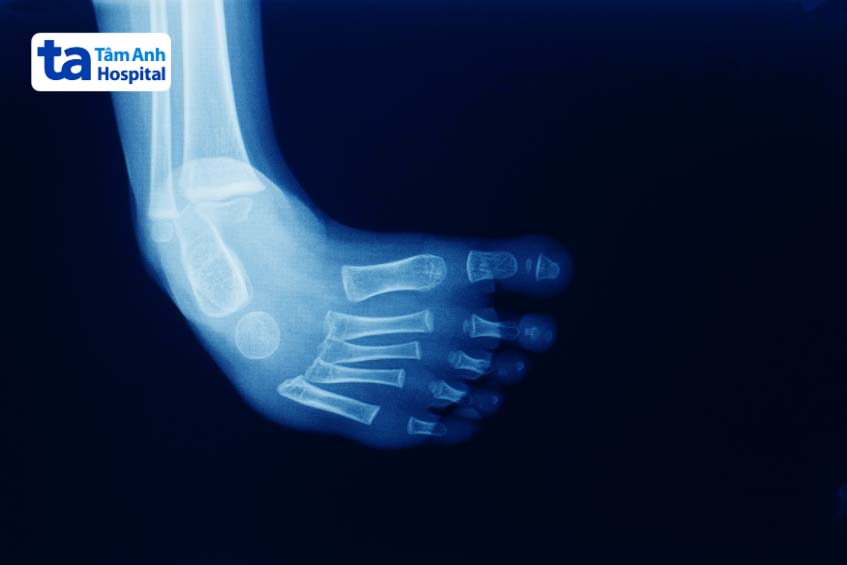

Bàn chân khoèo là một dạng dị tật bẩm sinh với biểu hiện đặc trưng là bàn chân xoay vào trong và hướng xuống dưới, thay vì nằm cân bằng ở tư thế như bình thường. Tình trạng này có thể xảy ra ở một hoặc cả hai bên chân và thường được chẩn đoán ngay sau khi trẻ chào đời.

Bàn chân khoèo xảy ra do gân ở bàn chân (các mô liên kết cơ với xương) ngắn và chặt hơn bình thường, làm cho cấu trúc bàn chân bị vẹo.